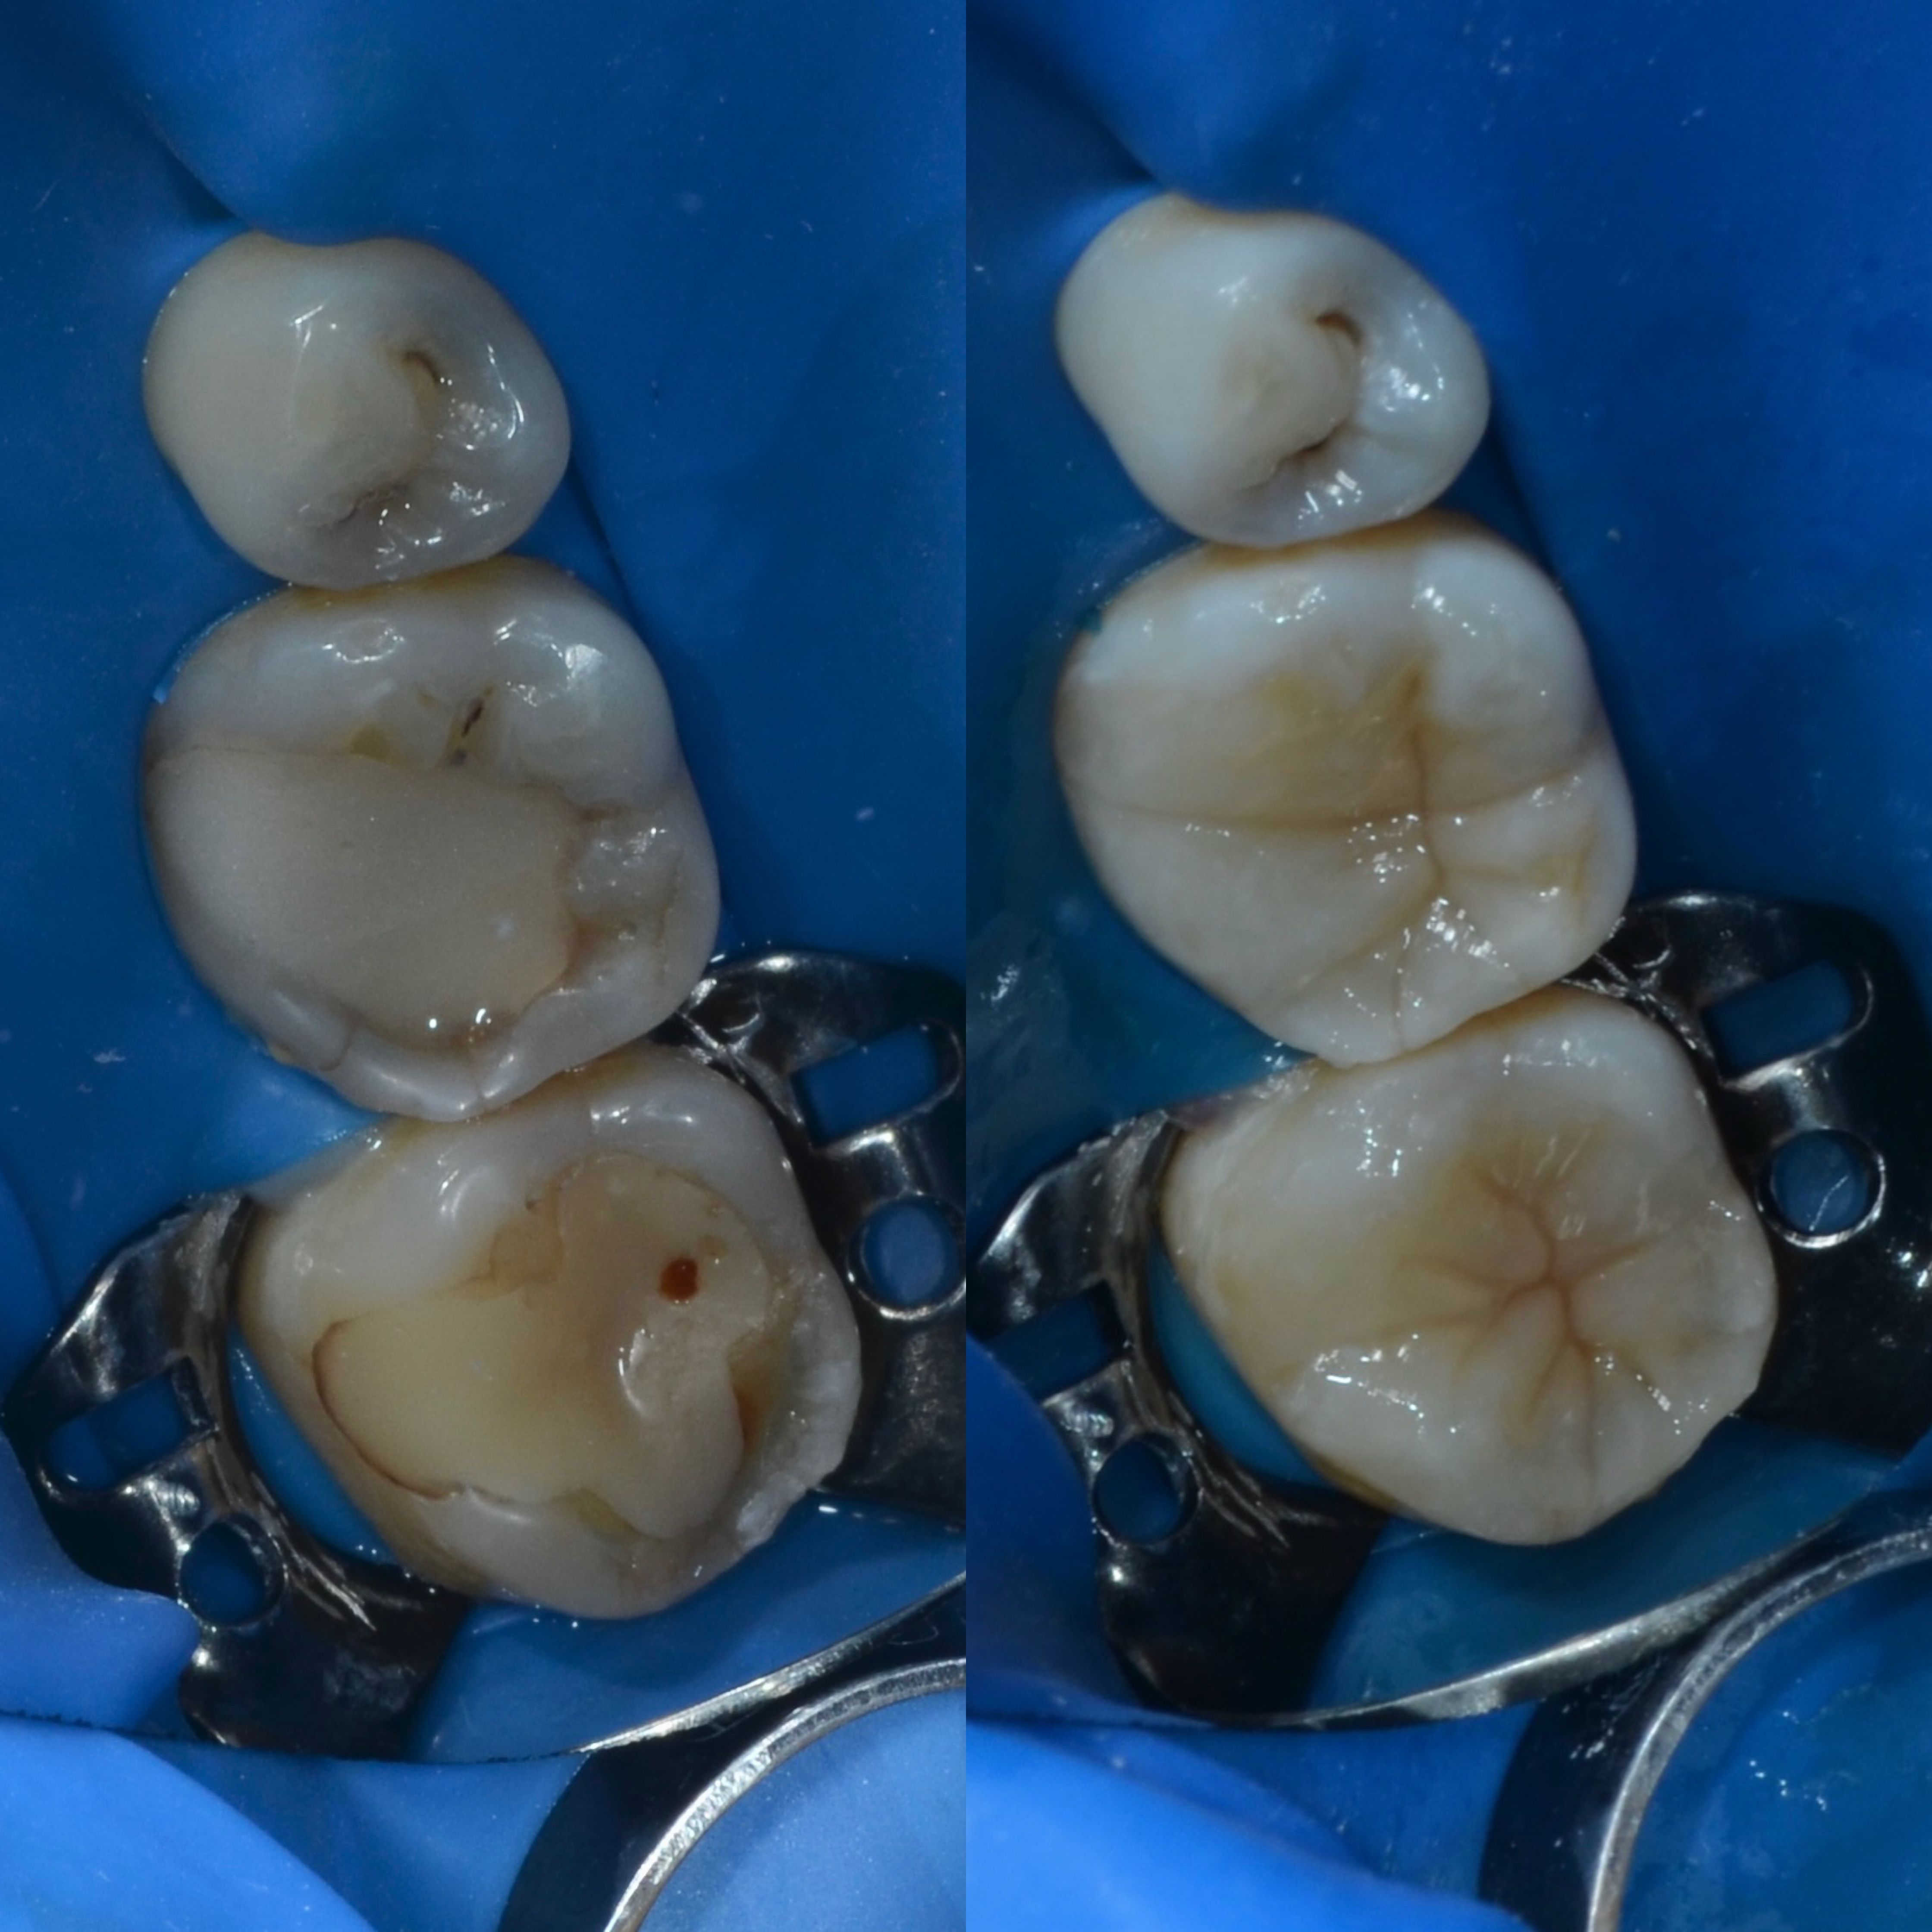

Лечение кариеса